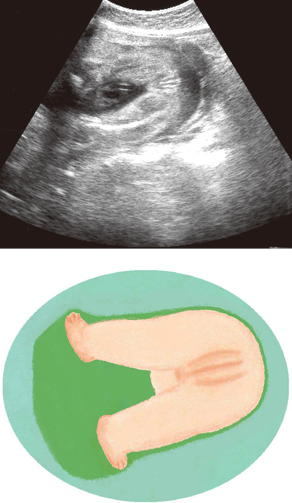

妊娠27週ころの超音波写真

女の子である印が見えます

外陰部を表すリップサインは女の子の印。外性器が突出していないので、わかりづらいでしょう。ちなみに超音波検査は性別判定のためではなく、赤ちゃんの発育を診る検査です。